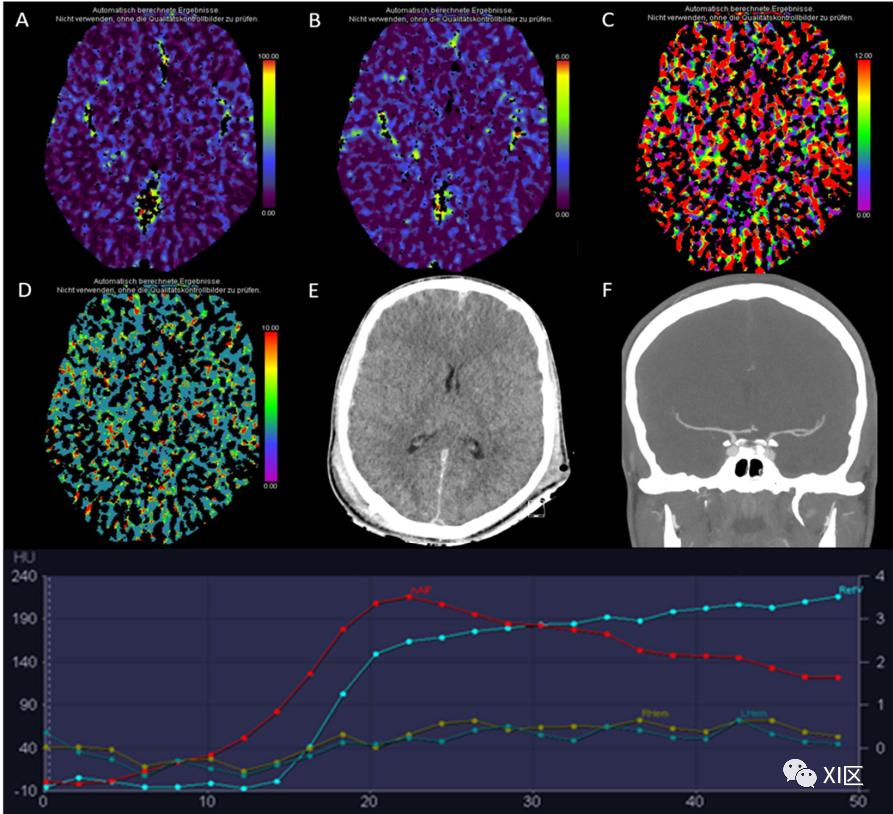

图1、图2、图3和图4给出了急性幕上卒中的例子。图5是一个恶性右侧MCA梗死的随访检查。

图1 脑部CTP产生的彩色编码图:(A)脑血流量量(CBF)[mL/100 g/min],(B)脑血容量(CBV)[mL/100 g],(C)Tmax [s],以及(D)平均通过时间(MTT)[s]。(E)CT平扫(NECT)和(F)动脉CT血管成像(CTA)。该患者接受了心导管检查,以关闭房间隔缺损。之后,该患者出现了左侧偏瘫。NECT显示灰白质分化略有减少。在右侧的大脑中动脉(MCA)区域,CBF和CBV降低,Tmax和MTT延长。CTA显示右侧颈内动脉远端闭塞。